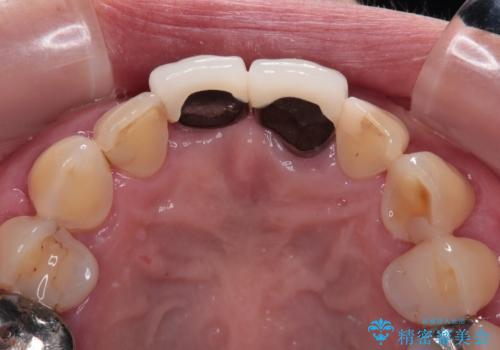

- 歯肉ラインの段差や、歯根が黒く見えている前歯を気にして来院された患者様です。

前歯のインプラントは埋入されたポジションが望ましい位置ではなく、インプラントを活用して段差を回収することは不可能と判断し、歯肉移植によりインプラントを隠して、ブリッジにて歯肉ラインを整えることとしました。

臼歯部の治療も必要と判断されましたが、前歯部を中心とした審美領域をオールセラミッククラウンによる補綴治療を行うこととしました。